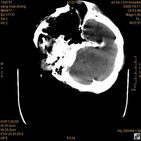

病人杨XX,男,青云街道办事处路踏泉村,住院号51666,CT号:104770。病人因“高血压脑出血”在新泰市人民医院住院治疗5天,治疗效果不佳转入我院,复查CT示左基底节血肿,病人昏迷状态,给予血肿清除术,术后2天复查CT,血肿完全清除,病人恢复好,治疗效果满意。附病人术前术后CT片资料如下。

术前CT

术前CT1 术前CT2 术前CT3 术前CT4